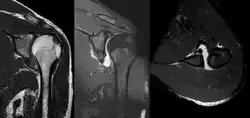

A diagnosis of shoulder dislocation is often suspected based on the person's history and physical examination. Radiographs are made to confirm the diagnosis. Most dislocations are apparent on radiographs showing incongruence of the glenohumeral joint. Posterior dislocations may be hard to detect on standard AP radiographs, but are more readily detected on other views. After reduction, radiographs are usually repeated to confirm successful reduction and to detect bone damage. After repeated shoulder dislocations, an MRI scan may be used to assess soft tissue damage. In regards to recurrent dislocations, the apprehension test (anterior instability) and sulcus sign (inferior instability) are useful methods for determining predisposition to future dislocation.

A Hill–Sachs lesion is an impaction of the head of the humerus left by the glenoid rim during dislocation.[6] Hill-Sachs deformities occur in 35–40% of anterior dislocations. They can be seen on a front-facing X-ray when the arm is in internal rotation.[11] Bankart lesions are disruptions of the glenoid labrum with or without an avulsion of bone fragment.[12]

-

An anterior dislocation of the shoulder